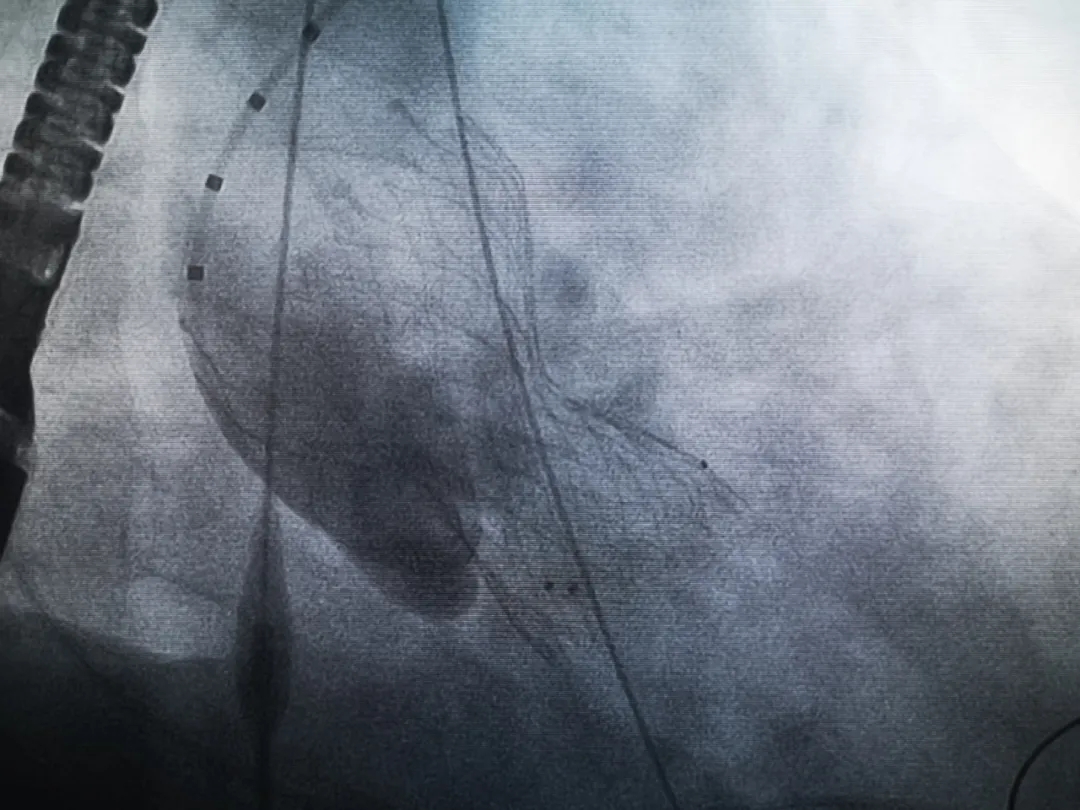

王子的手術(shù)被安排在周五。術(shù)前一天,TAVR團隊再次碰頭討論,從麻醉中血壓控制、球囊擴張、瓣膜釋放,到各種可能突發(fā)狀況的應(yīng)對,都提前制定了方案。尤其是瓣膜鈣化極為嚴重,對于擴張球囊型號的選擇、擴張的力度以及瓣膜植入后瓣周漏的發(fā)生預(yù)測,都具有很大挑戰(zhàn)。然而,如果沒有這些挑戰(zhàn),他又何必選擇我們呢!

手術(shù)過程緊張而有序,心臟沒有停跳,也沒有太大的血壓波動;球囊擴張的恰到好處,瓣膜釋放之后超聲醫(yī)生的評估是至關(guān)重要的,因為我們提前就準備了后擴張,也準備了瓣中瓣,甚至還準備了瓣周漏封堵。所幸的是,超聲診療中心劉夢梅醫(yī)生說:沒有返流、沒有瓣周漏,瓣膜形態(tài)良好,跨瓣壓差約17mmHg(相較于術(shù)前的87mmHg還是可以接受的)。瓣膜置入的成功并不是慶祝的時候,從戰(zhàn)場撤退仍然需要謹慎。由于王子特別胖,腹股溝區(qū)脂肪尤為肥厚,在股動脈插管拔除、確認搏動正常之后,便逐層縫合。同時為了美觀、縫合之后不至于鼓個包出來,我們又仔細剪除了部分脂肪。術(shù)后次日,王子便可以下床活動了。